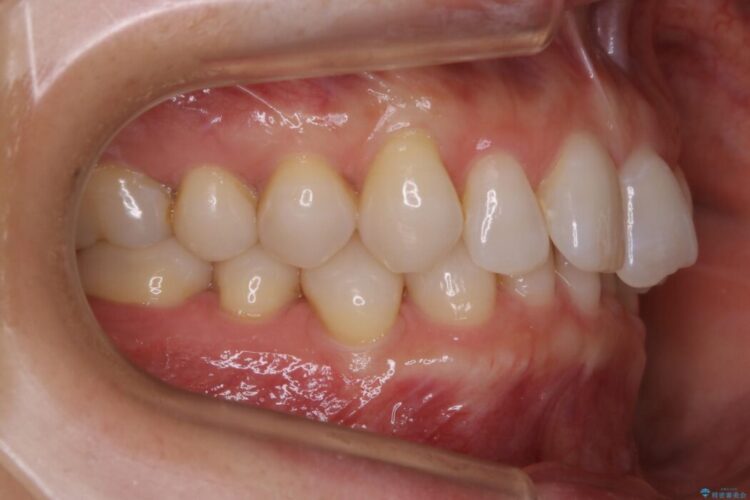

主訴としては矯正治療にて歯列を整えることでした。

悪くなっている歯の放置はできないと判断しましたので、患者様と様々な治療プランを相談した上で、最終的に該当の歯は抜歯をして噛み合わせを改善し、その後インビザラインでの矯正治療を行うこととしました。

噛み合わせも改善され、一番最初の目的であった歯列もきれいに整いご満足いただけました。